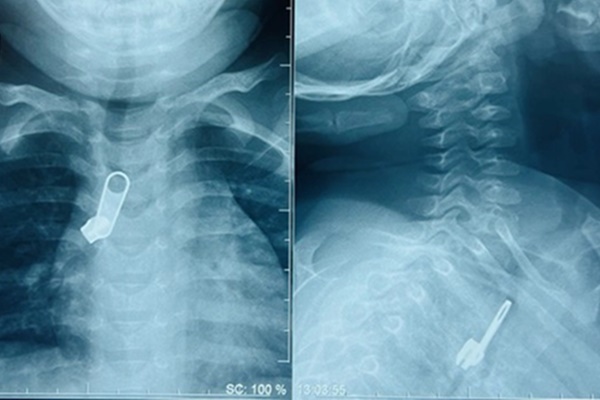

Bác sĩ phát hiện bé có lỗ tiểu lệch thấp, bìu chẻ đôi khiến dương vật bị vùi giữa 2 bên bìu, trông giống âm vật kèm theo hai tinh hoàn chưa xuống bìu, nằm trong ống bẹn. Đây là lí do khiến khi sinh ra, bé bị nhầm lẫn giới tính.

Bé được làm thêm các xét nghiệm xác định giới tính như xét nghiệm gene nhiễm sắc thể, gene biệt hóa tinh hoàn và các xét nghiệm về nội tiết. "Kết quả các xét nghiệm đều xác định bé là trai", bác sĩ Hoa nói.

Một tuổi, bé được phẫu thuật hạ tinh hoàn 2 bên xuống bìu. Khi gần 2 tuổi, bác sĩ phẫu thuật tạo hình niệu đạo đưa lỗ tiểu thấp từ vị trí tầng sinh môn lên đỉnh quy đầu. Sau 10 ngày mổ, bé được rút ống thông tiểu và có thể đứng tiểu như bé trai bình thường. Ngày 27/3, gia đình cho biết đang chuẩn bị các thủ tục để đổi tên và giới tính trên giấy khai sinh cho cháu.